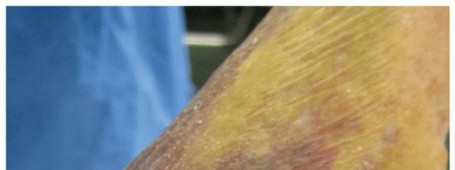

DEFINITION Posterosuperior tears of the rotator cuff involve the supraspinatus, infraspinatus, and occasional…